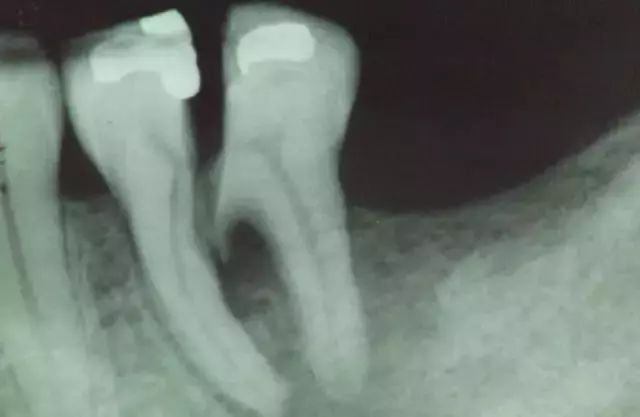

X光片下的牙隐裂

很多患者拖到牙齿彻底劈裂,或者拖到牙神经发炎,引起剧烈的疼痛后,才肯看牙医,那个时候牙齿可能已经保不住了。即使能保住,也花费不菲。

因此一旦发现了牙隐裂的苗头,应尽快去找牙医检查。越早检查,牙齿的治疗会越简单。